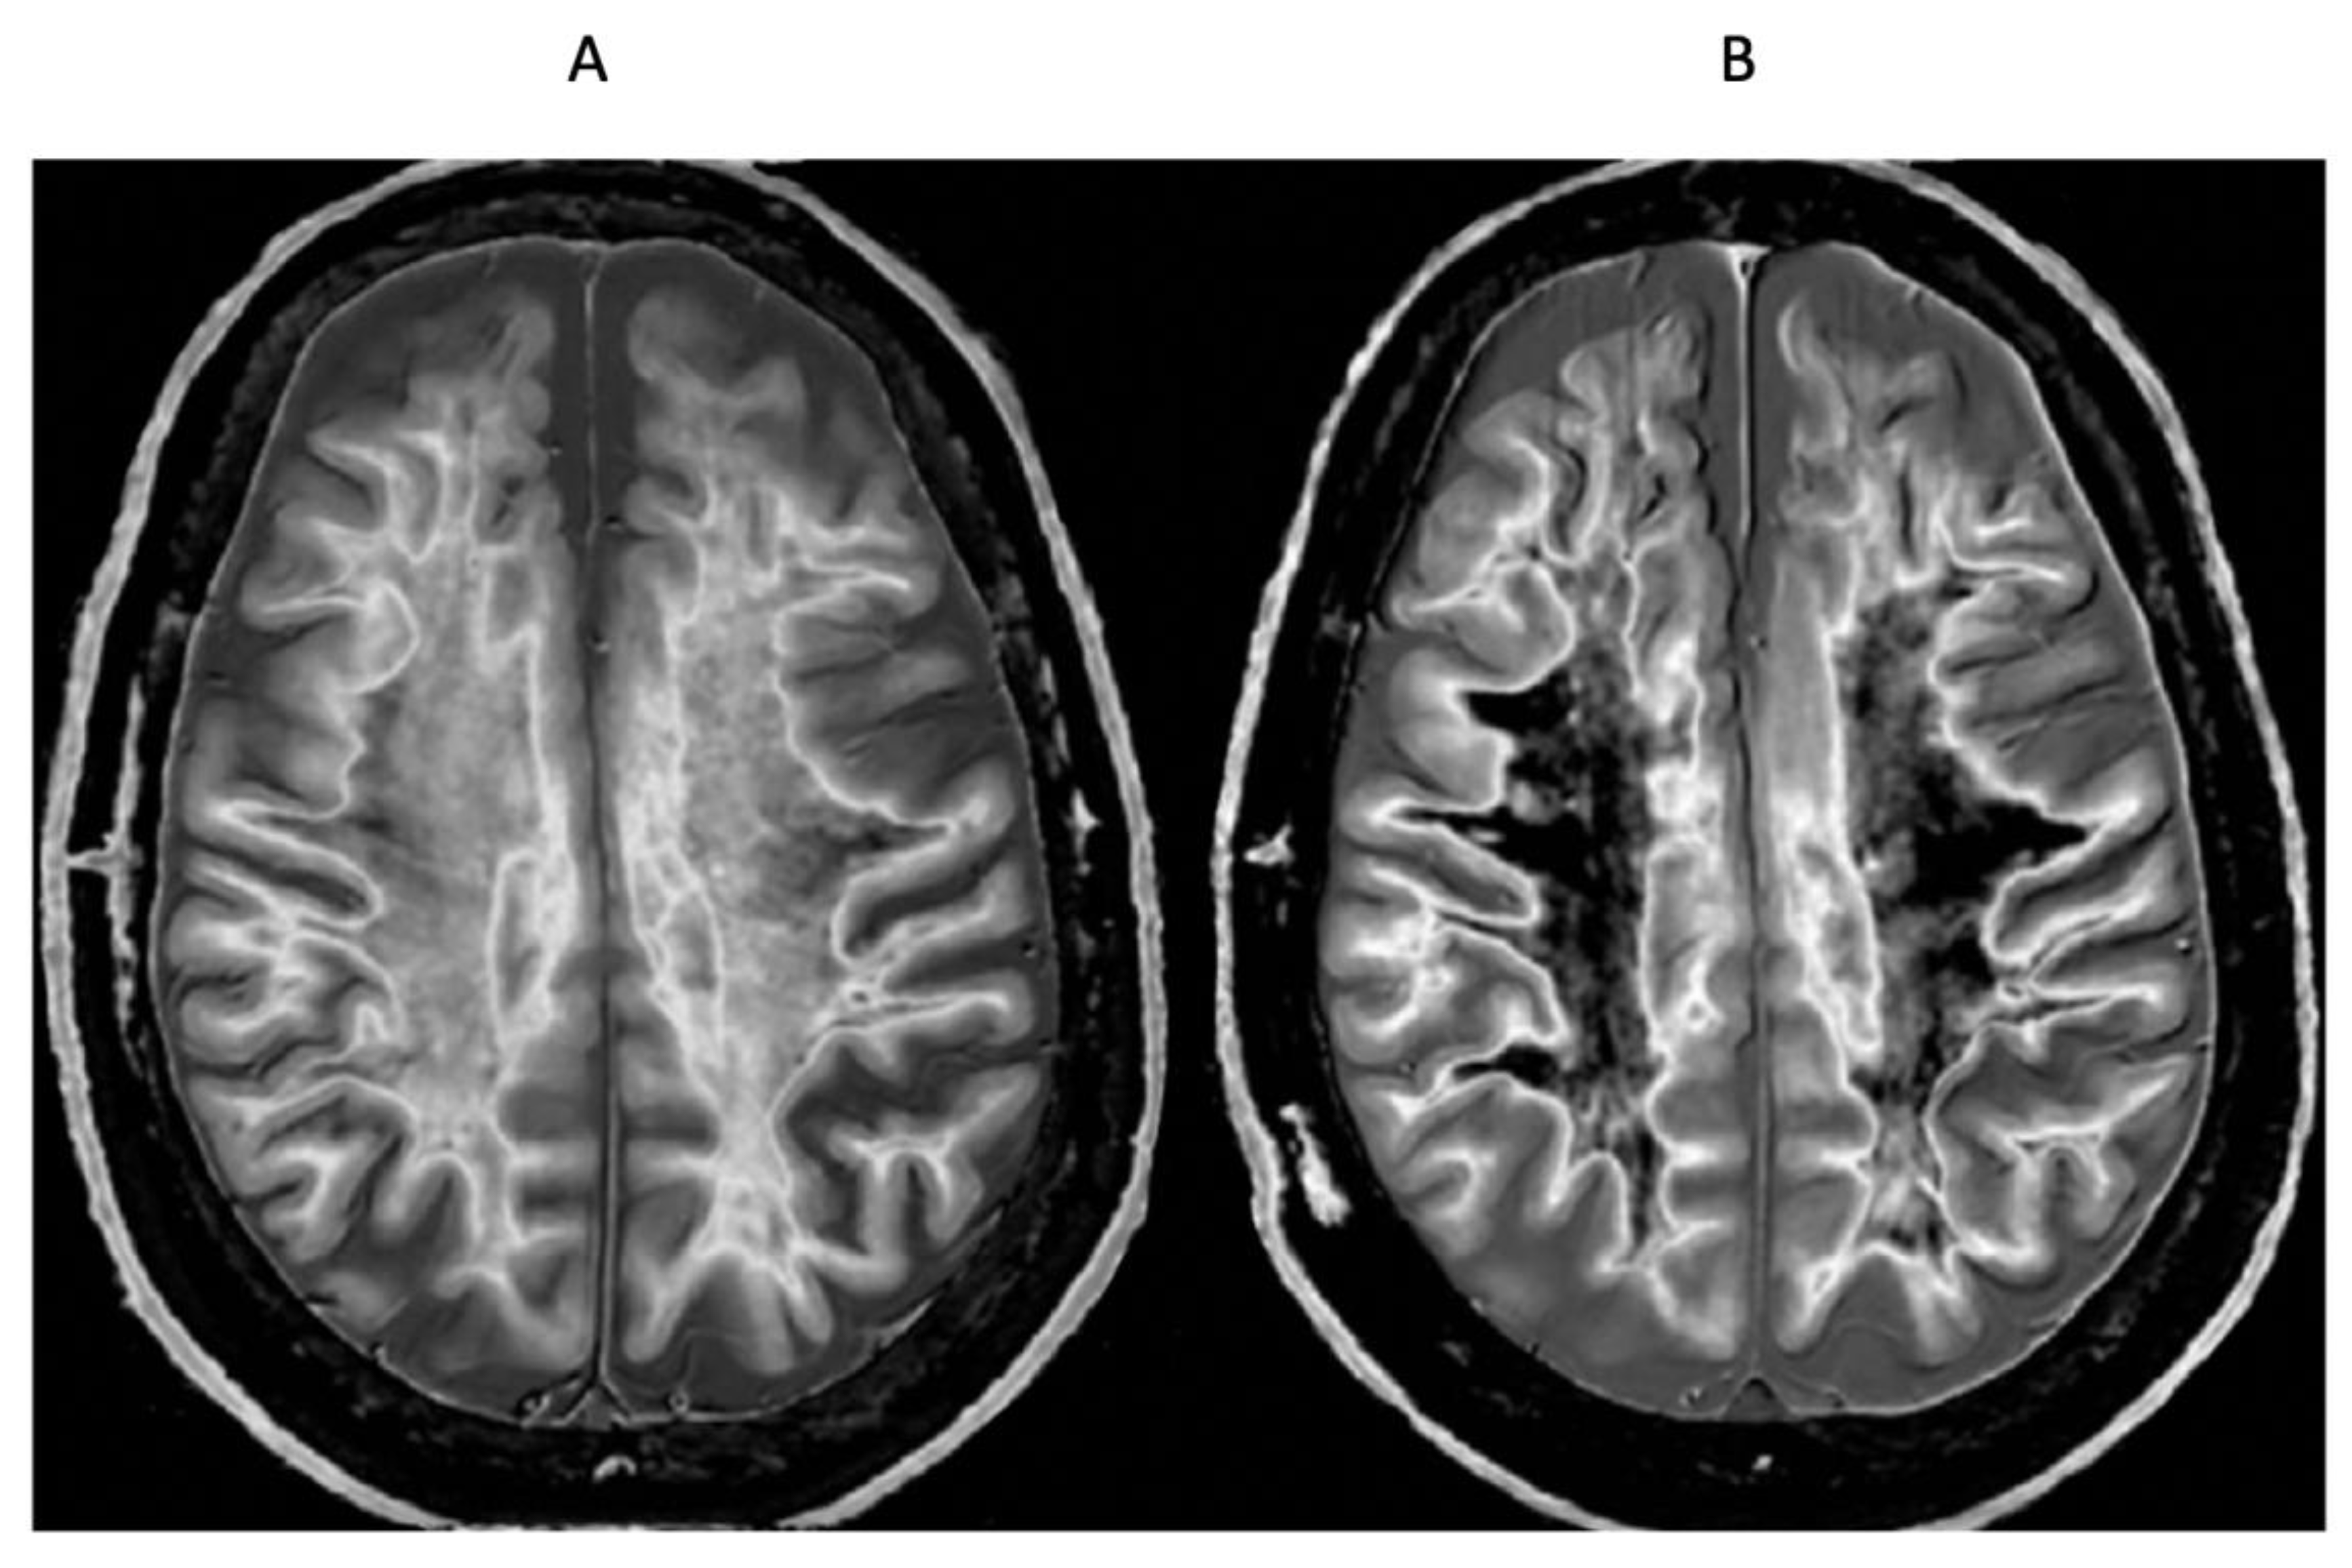

- Ultra-high contrast MRI using bipolar filters (BLAIRs) can show abnormalities with very high contrast where little or no change from normal is seen with common conventional state-of-the-art sequences.

- The abnormalities shown with ultra-high contrast are due to small changes in tissue properties such as T1 and T2 in disease. This is complementary to existing sequences which show abnormalities due to larger changes in T1 and T2 in disease.

- At boundaries between tissues and fluids on ultra-high contrast images there is frequently an increase in contrast and an increase in the spatial resolution of that contrast.

- Extensive abnormalities were seen in mild traumatic brain injury, multiple sclerosis and white matter associated with cerebral tumours in the absence of changes in T2-weighted spin echo or T2-FLAIR images.